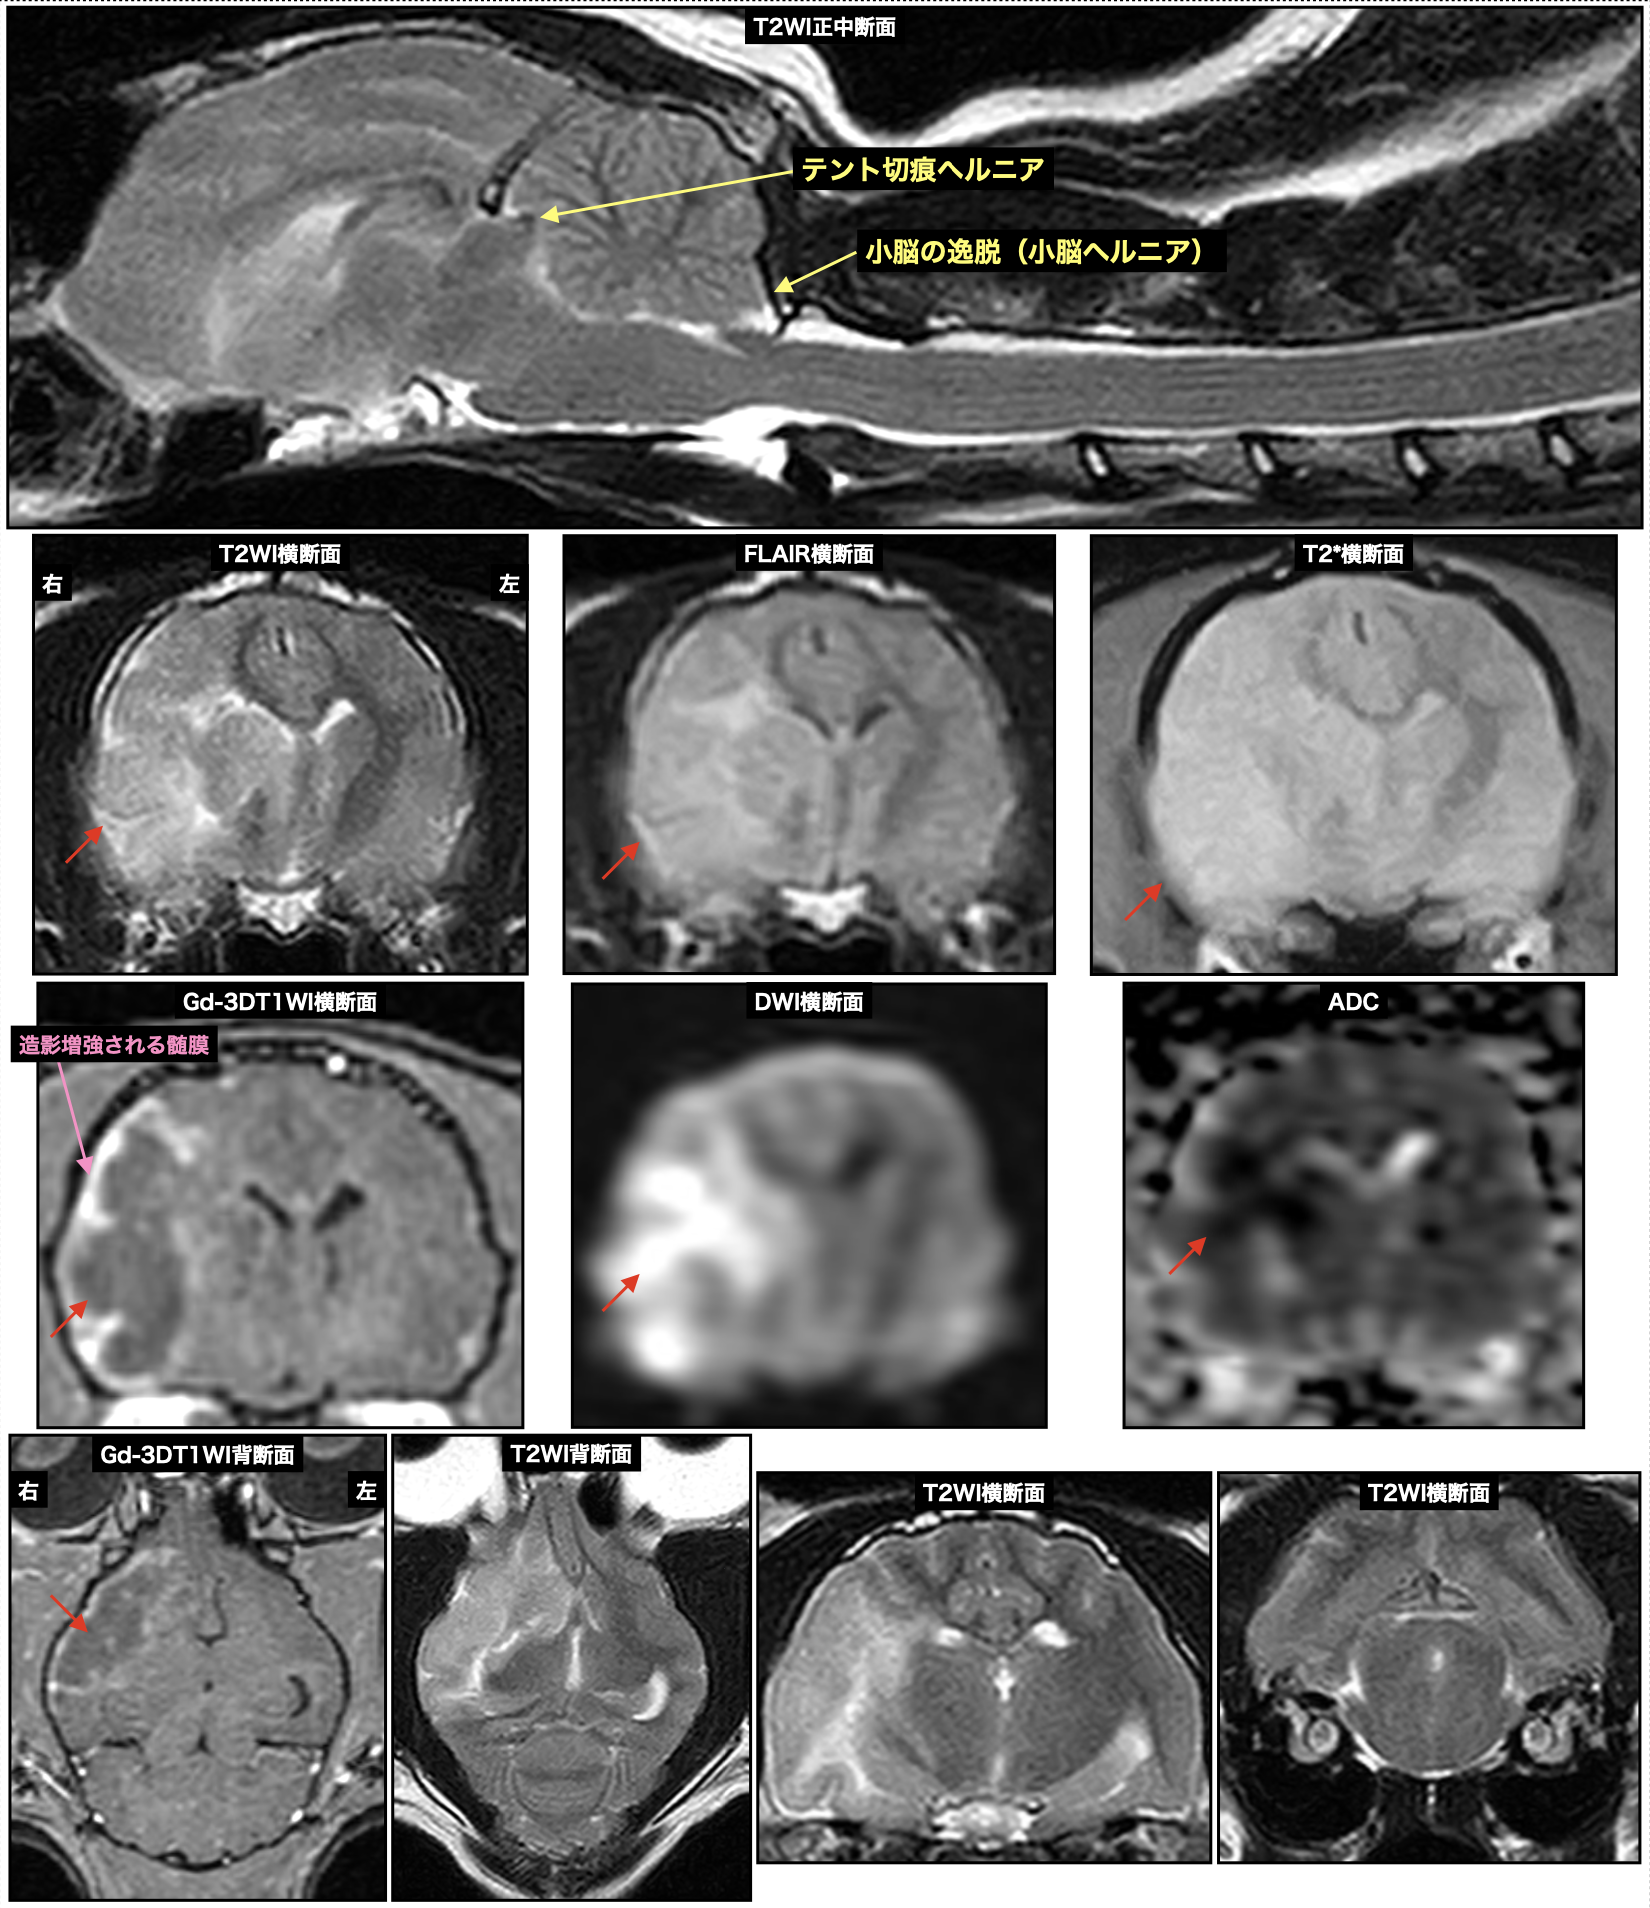

右中大脳動脈における脳梗塞を疑った8歳の日本猫、症状は急性の左半身麻痺・意識レベル低下